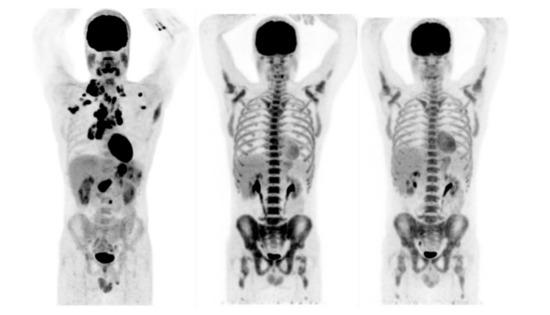

Relating to the assessment of tumor response at interim, 14 patients (70%) showed CMR, while the remaining 6 patients (30%) had PMR. Relating to the assessment of tumor response at the EOT, 15 patients (75%) showed CMR, 3 (15%) had PMR, and 2 (10%) had PMD (see Table 3). In Figure 2, maximum intensity projection (MIP) of PET images at baseline, at interim and at the EOT for a patient showing CMR both at T1 and T2 are shown.

Figure 2. Maximum intensity projection (MIP) of positron emission tomography (PET) images at baseline, at interim and at the end-of-treatment (EOT) for a patient showing complete metabolic response (CMR), according to Lugano evaluation, both at T1 and T2.